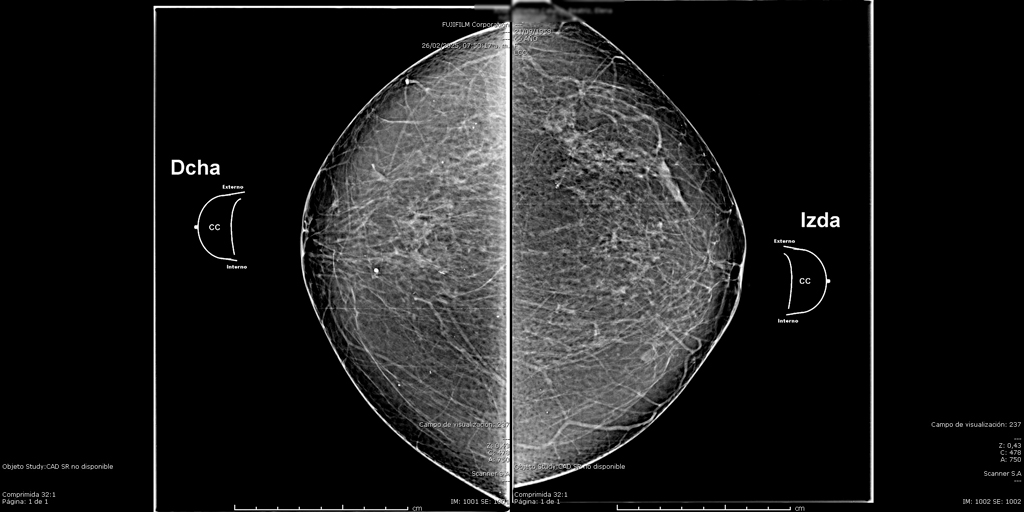

La mamografía es un estudio de diagnóstico por imagen que utiliza bajas dosis de rayos X para obtener imágenes detalladas del tejido mamario. Es una herramienta fundamental para la detección temprana del cáncer de mama y otras patologías mamarias, incluso antes de que sean evidentes al tacto o generen síntomas. Su uso regular en controles preventivos permite salvar vidas al facilitar diagnósticos oportunos y tratamientos más efectivos.

En SCANNER S.A, nuestros equipos digitalizados permiten detectar cambios mínimos en el tejido mamario con alta claridad, permitiendo asi tener un diagnostico preciso y entregar unos resultados reales a nuestros pacientes.